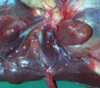

mandibular salivary gland